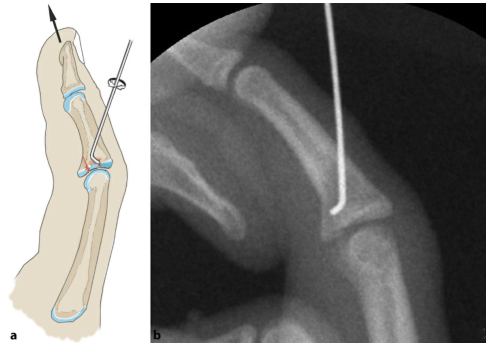

1. Схема модели чрескожной операции по уменьшению и фиксации стальными штифтами:

Применяют методику репозиции Хинтрингера и Эндера: сжатый костный фрагмент удаляют из костномозговой полости через дорсальное костное окно. Потяните вперед и согните проксимальный межфаланговый сустав на 20–30 градусов, чтобы уменьшить подвывих. Зафиксируйте костный фрагмент и проверьте устойчивость пальца в разогнутом положении. Если сохраняется тыльный подвывих средней фаланги, необходимо также заблокировать шкив, в котором в фалангу вводится стальной штифт.

2) Чем выше нестабильность сустава (например, перелом III типа), тем раньше следует использовать блокирующий штифт. (Как показано ниже)